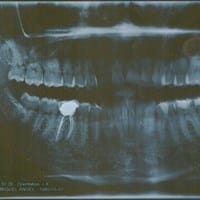

Tengo una infección endodóntica que no aparece en la radiografía

Hola! Hace poco mas de un año me hicieron una endodoncia, pero resulta que hace aproximadamente un mes empecé a sentir una ligera molestia hasta que se convirtió en fuerte dolor de muela e inflamación en la cara. Fui con la endodoncista que me...